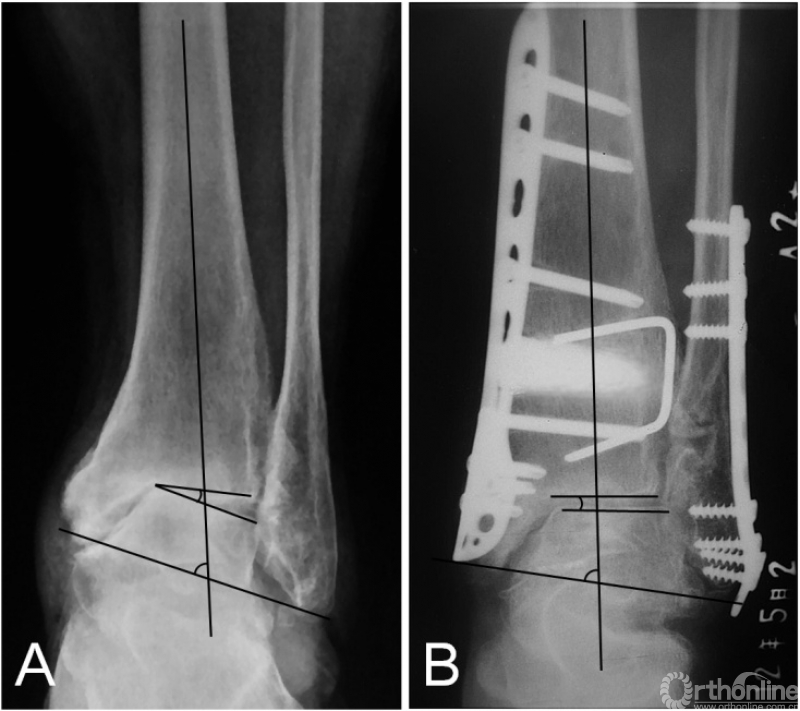

在踝上截骨时,是否及何时需要辅助腓骨截骨目前尚无定论。在早期的报道中,腓骨截骨被要求作为常规术式来矫正踝关节内翻畸形[19-21];然而,后来的一些研究则要求在所有患者中保留腓骨[6,11,13,15]。而我们只在需要时才辅助腓骨截骨,评估内容分为术前和术中。术前评估包括:1)患侧TC角较健侧减小超过5°或存在内翻改变;2)存在腓骨骨折畸形愈合;3)患者因胫骨骨骺损伤史而导致腓骨相对较长。术中主要评估在胫骨远端关节面积距骨复位时,是否存在外侧阻挡。生物力学研究指出,在胫骨远端关节面外翻时,胫距关节的接触压强并未随之显著外移,而是在内侧形成峰值压强;只有在腓骨截骨后,胫距关节的接触压强才随着外翻角度的增大逐渐转向外侧[24]。因此,在这种情况下,腓骨截骨可以促进关节协调性的恢复,以及接触压力的外移[12]。根据我们的研究结果,腓骨截骨组的患者,TT角的改善程度更加显著(图3)。尽管两组的术后平均TT角基本一致,这正说明在腓骨截骨组,患者的术前内翻畸形更加显著。另外,我们的研究也发现腓骨截骨组的TC角改善更加明显。

图3 术前X线片提示内翻型踝关节骨关节炎(3B期),行踝上截骨合并腓骨截骨术后2年,患者的关节匹配度及负重力线均矫正良好,距骨倾斜角从术前的14.5°降至1.2°。